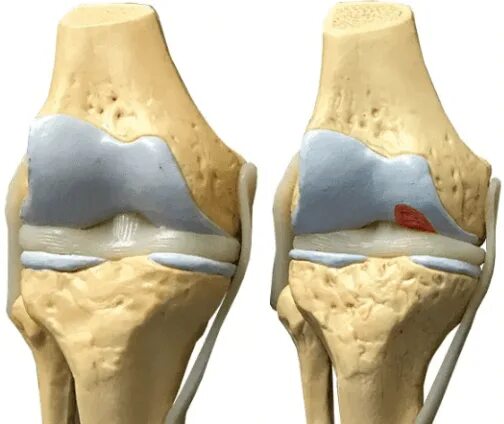

Явления остеоартроза